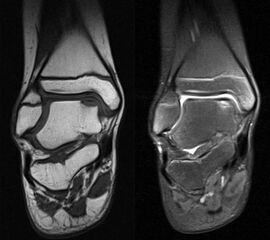

MRT

Die Kernspintomographie hat ihre Stärke in der Darstellung von Weichteilverletzungen. Insbesondere Verletzungen der Wachstumsfuge, des Periosts und der Bänder lassen sich gut visualisieren. Nachteilig ist die Untersuchungsdauer von 20-30 Minuten. Bleibt das Kind während dieser Zeit nicht ruhig liegen, kommt es zu Bewegungsartefakten, welche die Beurteilbarkeit der Bilder beeinträchtigen.

Fugengelenkfrakturen treten typischerweise vor dem 10. Lebensjahr auf, in einer Phase, in welcher die Wachstumsfugen noch weit offen sind. Dieser Frakturtyp betrifft fast ausschließlich den medialen Malleolus. Laterale Frakturen sind extrem selten, teilweise kommt es zu lateralen Bandverletzungen oder Fugenschaftfrakturen der distalen Fibula. Die Frakturlinie verläuft in einer Verlängerungslinie von der medialen Taluskante nach proximal. Häufig stellen sich Verletzungen des Innenknöchels im Röntgenbild schlechter dar, insbesondere wenn die Aufnahmen verdreht sind oder die Ebene der Fraktur bei geringer Dislokation verkippt zur Röntgenebene liegt. Besteht klinisch der geringste Hinweis auf eine Verletzung des Innenknöchels, muss aufgrund der Tragweite der Verletzung durch entsprechende Aufnahmen gegebenenfalls auch Schnittbildverfahren die Verletzung sicher diagnostiziert oder ausgeschlossen werden (Abb. 15).